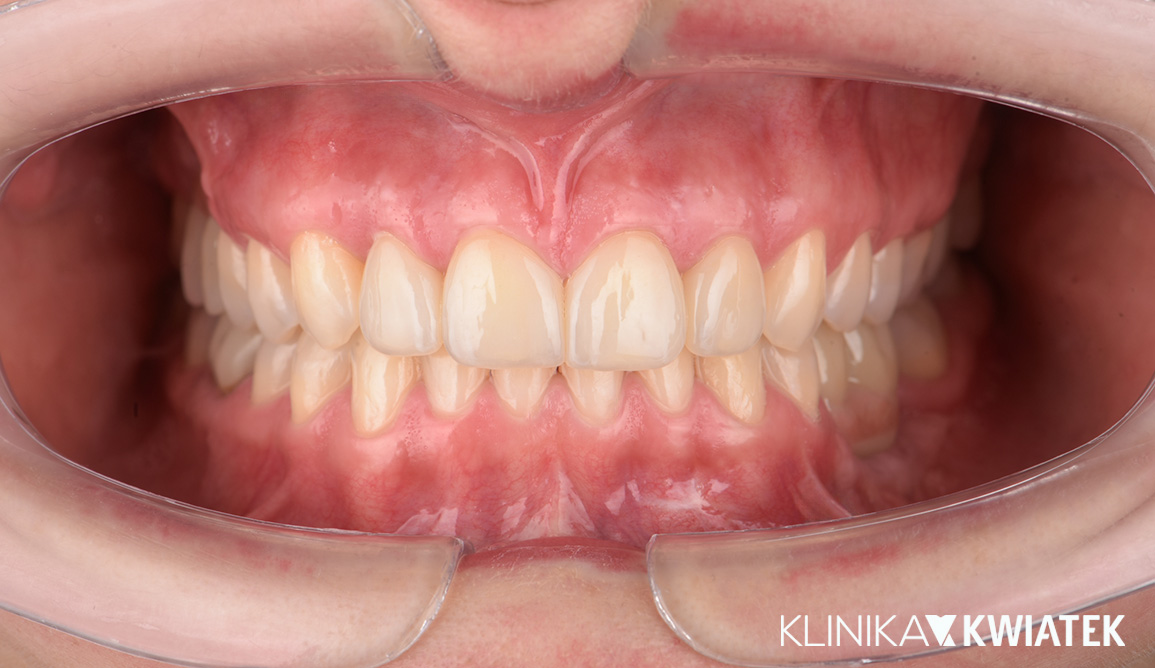

PO

Pan Jakub zgłosił się do kliniki z wadą zgryzu oraz licznymi problemami wynikającymi z nieprawidłowego ustawienia zębów. Leczenie wymagało współpracy specjalistów z kilku dziedzin stomatologii, precyzyjnego planowania oraz konsekwentnej realizacji kolejnych etapów terapii.

Dzięki ogromnej determinacji Pacjenta, który pomimo dużej odległości regularnie przyjeżdżał na zaplanowane wizyty, możliwe było przeprowadzenie kompleksowego leczenia, którego efektem jest doskonale zbalansowany zgryz oraz spektakularna i w pełni naturalna metamorfoza uśmiechu.